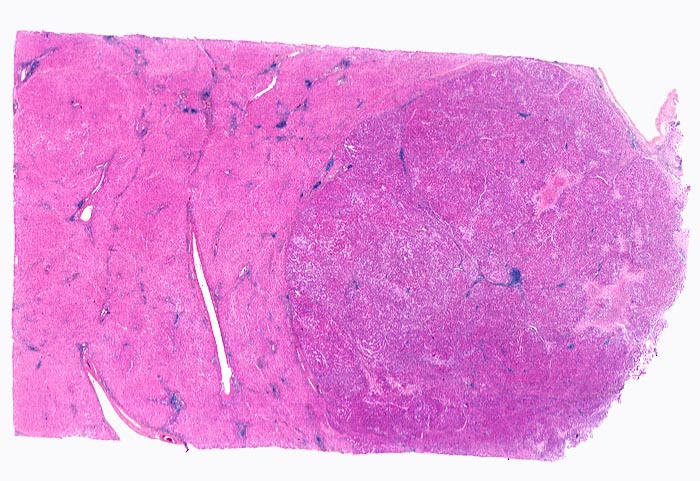

PathoPic – image database / PathoPic ID 4398 - hepatozelluläres Karzinom bei chronischer Hepatitis C

hepatozelluläres Karzinom bei chronischer Hepatitis C

Das Leberparenchym links im Bild zeigt entzündlich infiltrierte und fibrosierte Portalfelder als Folge der chronischen Hepatitis C. Der scharf begrenzte Tumor rechts im Bild ist aufgrund der höheren Kern-Zytoplasmarelation dunkler gefärbt. Im Tumor finden sich lediglich Arterien, aber keine Portalfelder. Fokale Tumornekrosen und intratumorale Entzündungsinfiltrate.

Patient mit bekannter chronischer Hepatitis C. Bei einer sonographischen Kontrolluntersuchung wird ein 1cm grosser Knoten entdeckt. Das Alpha-Fetoprotein im Serum ist nicht erhöht.

Das hepatozelluläre Karzinom kann scharf oder unscharf begrenzt sein. Scharf begrenzte Tumoren können bekapselt sein. Die Tumorknoten können solitär oder multipel sein und im letzteren Fall wie ein zirrhotischer Umbau imponieren.